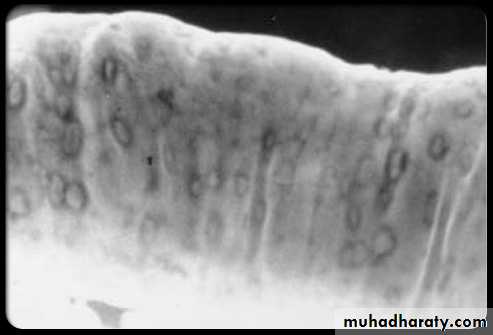

The central barium collections (ulcer crater) and mounds of edema are characteristic of aphthous ulcers.A cobblestone mucosal pattern affects a nonstenotic segment of small bowel

small bowel.b. Ulcers may be deep +/- cobblestoning

Multiple discrete ulcerations are present in the distal small bowel.